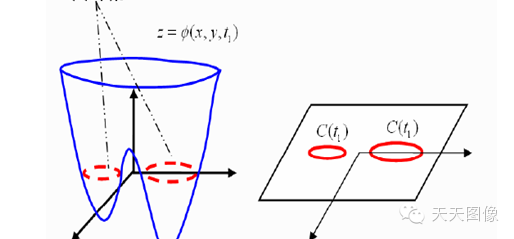

那么水平集算法的核心思想是什么嗯?那就是将要研究的问题,看做是更高一维空间的函数(也就是水平集函数)的零水平集。因此,当我们要追踪某一曲线(曲面)的演化过程,实际上就等价于追踪更高一维曲面的演化过程。

图2

如上图1至2的演化过程,如果对红色曲线建立一个随时间而变化的模型,是很困难的,因为发生了拓扑结构变化(一条曲线变成了两条),但是如果只是对蓝色的曲面建立随时间变化的过程,则是可行的,而红色曲线就是取其Z=0的水平集。